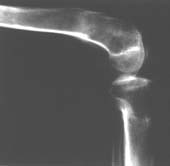

Пациент В. 53 лет, травма в феврале 2009. ДЗ. Открытый оскольчатый перелом нижней трети голени. При боли поступлении выполено ПХО, аппарат Илизарова. В последующем проводили ВХО, резекция костных отломков, укорочение 6 см, рана зажила. Была выполнена остеотомия большеберцовой кости в проксимальном отделе, резекция. Производилось тракция. На последних рентгенограммах выявлено, что одновременно с "выращиванием" регенерата произошло низведение надколенника на длину выращенного регенерата. Клинически: активное разгибание сохранено, объем движений в колене 180-110 градусов. Черными стрелками обозначен верхний край надколенника с одной и с другой стороны. Красная стрелка обозначает пальпируемую связку надколенника. Причина - остеотомия выше места прикрепления связки надколенника. Вопрос: была ли у кого подобная ситуация? Что делать? При первом обдумывании приходит решение: отсечение места прикрепления связки надколенника с костным блоком, перемещение на "правильное" место, укорочение сухожилия четырехглавой мышцы.

По снимкам - плотность регенерата хорошая, сложностей с фиксацией в него костного "основания" быть не должно.